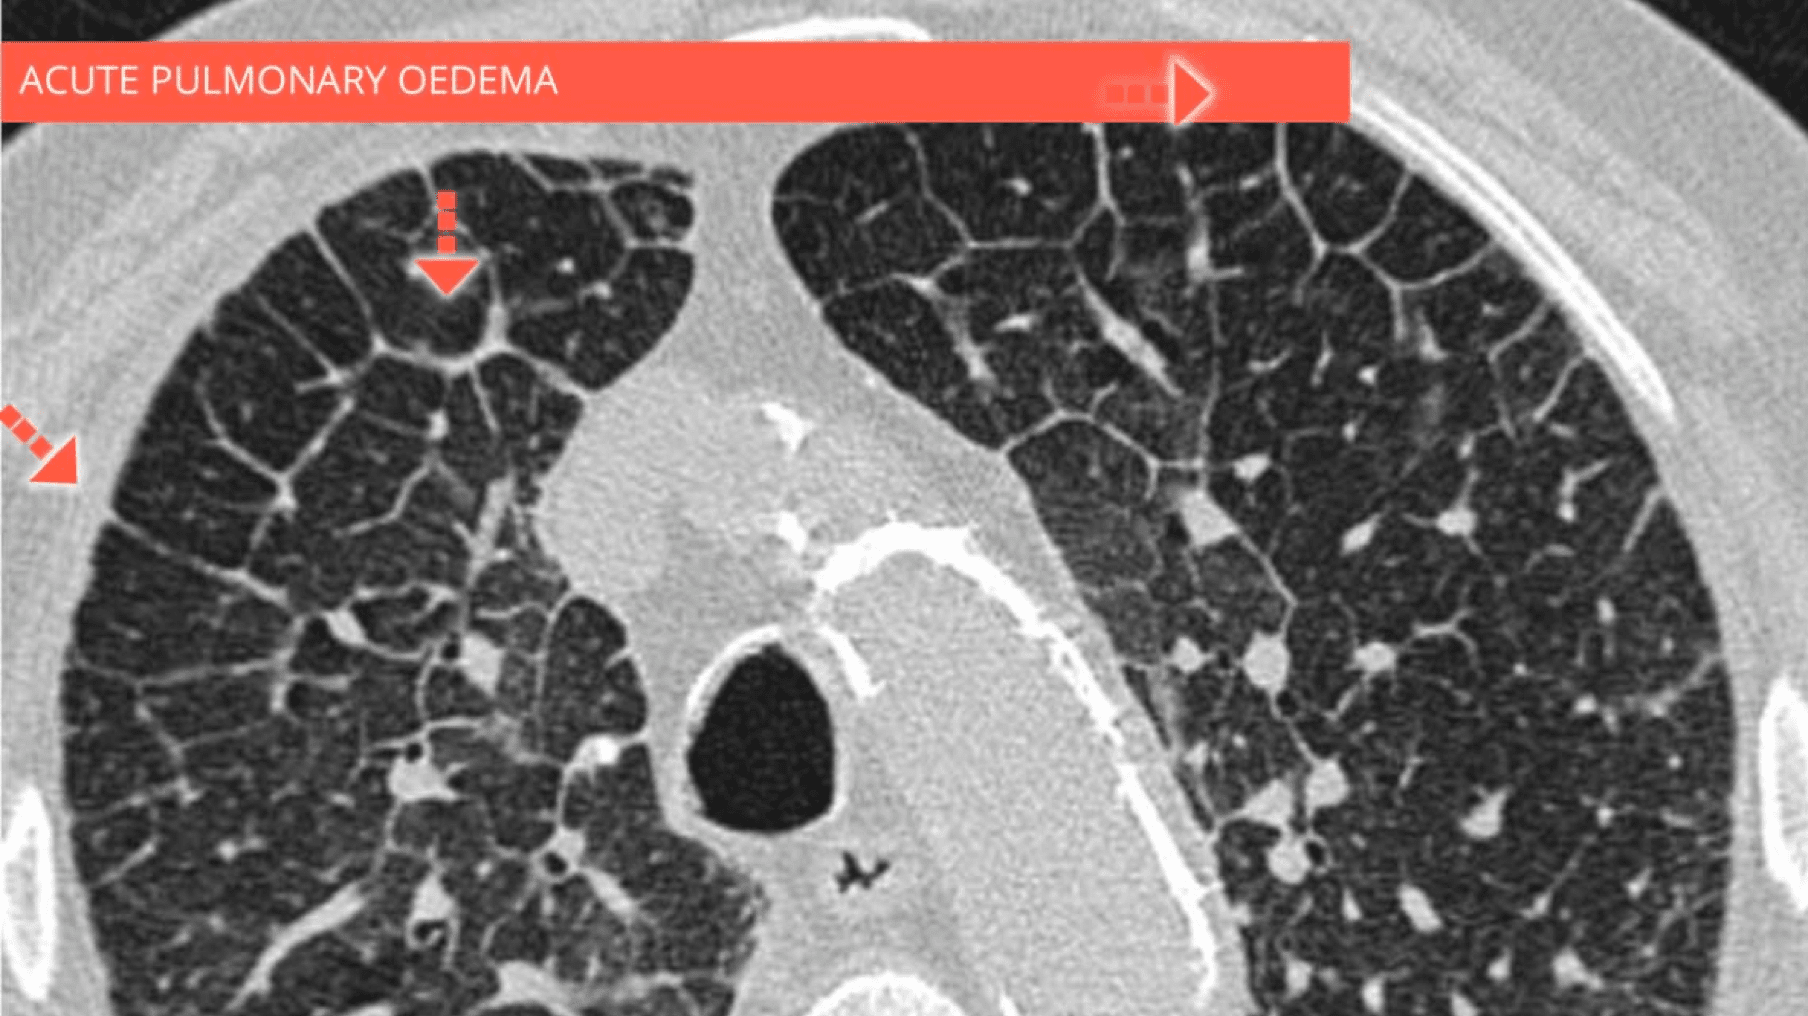

Interlobular septal thickening

Characteristics

• Thin linear opacities between lobules

• Length of lines: 10 - 20 mm

• Preferential location: subpleural

• Presentation: simple lines / polygons

Regular septal lines

Septal thickening forming polygons in the lung parenchyma